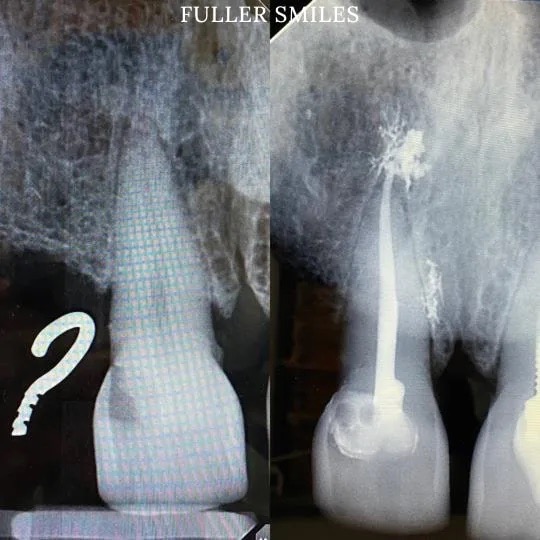

A thorough clinical exam, endodontic screening and proper x rays led to the diagnosis of irreversible pulpitis(inflamed pulp tissue) due to secondary dental caries with inflamed periodontal ligaments.

Our Dentists used the latest technology and highest quality products to finish this beautiful root canal followed by a post and core to give the tooth additional strength. The tooth was crowned after the root canal to restore function and aesthetics.